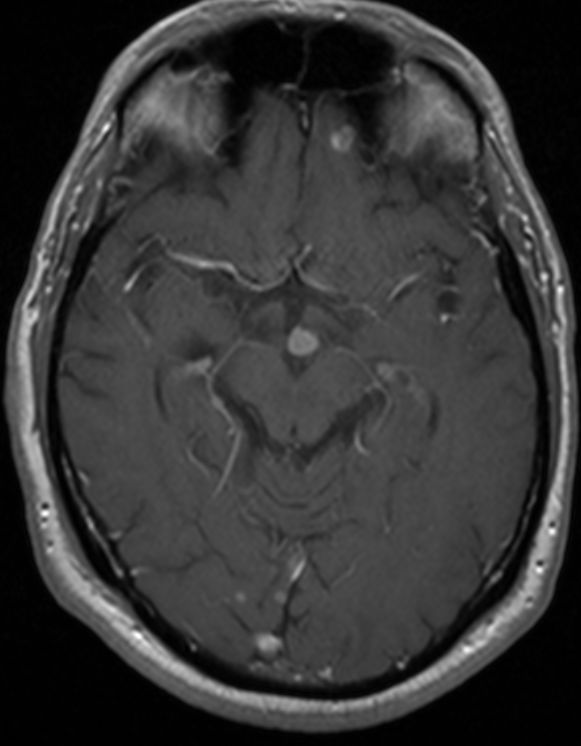

MRT: multiple Hirnmetastasen

70-jähriger Mann, der vor einem Jahr ein Adenokarzinom des rechten Lungenmittellappens hatte. MRT-Untersuchung des Hirns, T1-Sequenz mit Kontrastmittel. Klinisch keine Symptome!